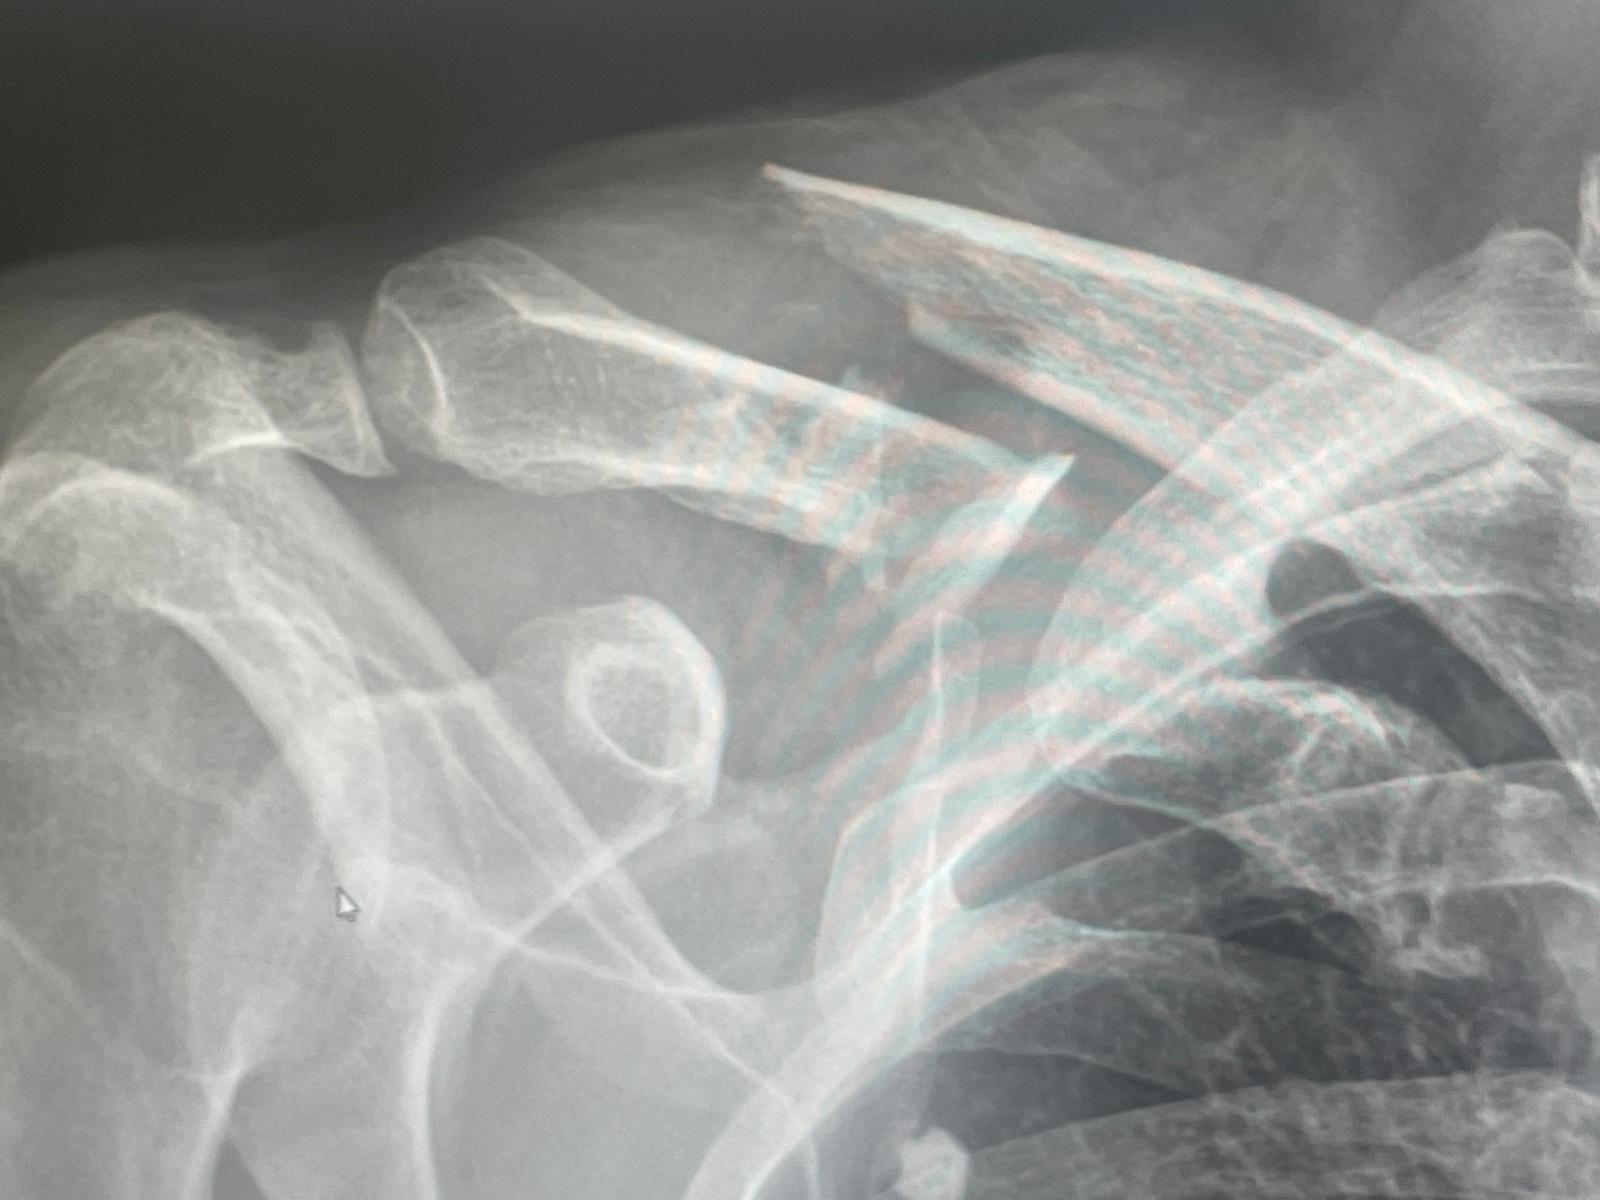

img-20250706-wa0001.jpg

The collarbone (clavicle) connects your shoulder to your sternum, playing a vital role in upper body mobility. When fractured, it typically requires immobilization, rest, and sometimes surgery. Recovery can take 6–12 weeks, depending on severity. But while the body rests, the mind often races—worrying about progress, pain, and the future.